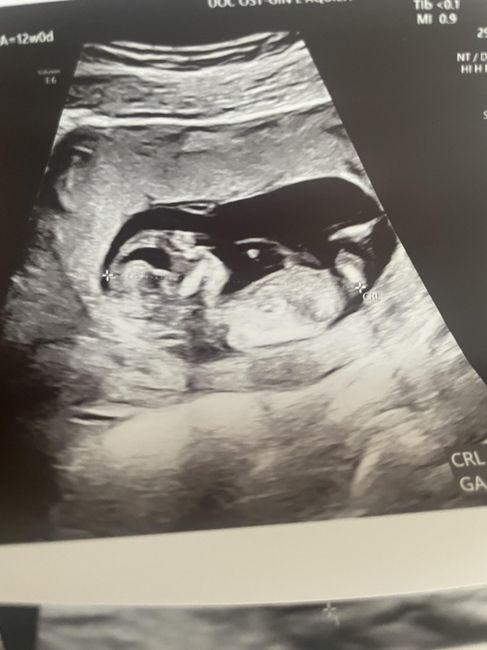

Nub theory, giochiamo un po’

Ciao ragazze, lunedì scorso ho fatto eco genetica a 11+5 ma bebè misurava 12 settimane, ho fatto dna fetale che dovrebbe arrivare questa settimana, ma nel frattempo per ingannare il tempo e l’ansia, c’è qualcuna che se ne intende di nub theory? Io un pochino sì e quindi ho una mia idea. Sia per il tubercolo, sia per la posizione della vescica, rispetto alla spina dorsale… ma magari qualcuna qui ne capisce più di me, maschio o femmina?vi lascio un po’ di foto

Nub theory, giochiamo un po’ 1

12+0 che pensate? Non si capisce 😅🙂‍↕️

Nub theory, giochiamo un po’ 2

Ecco qui quella di oggi… siamo a 12+3